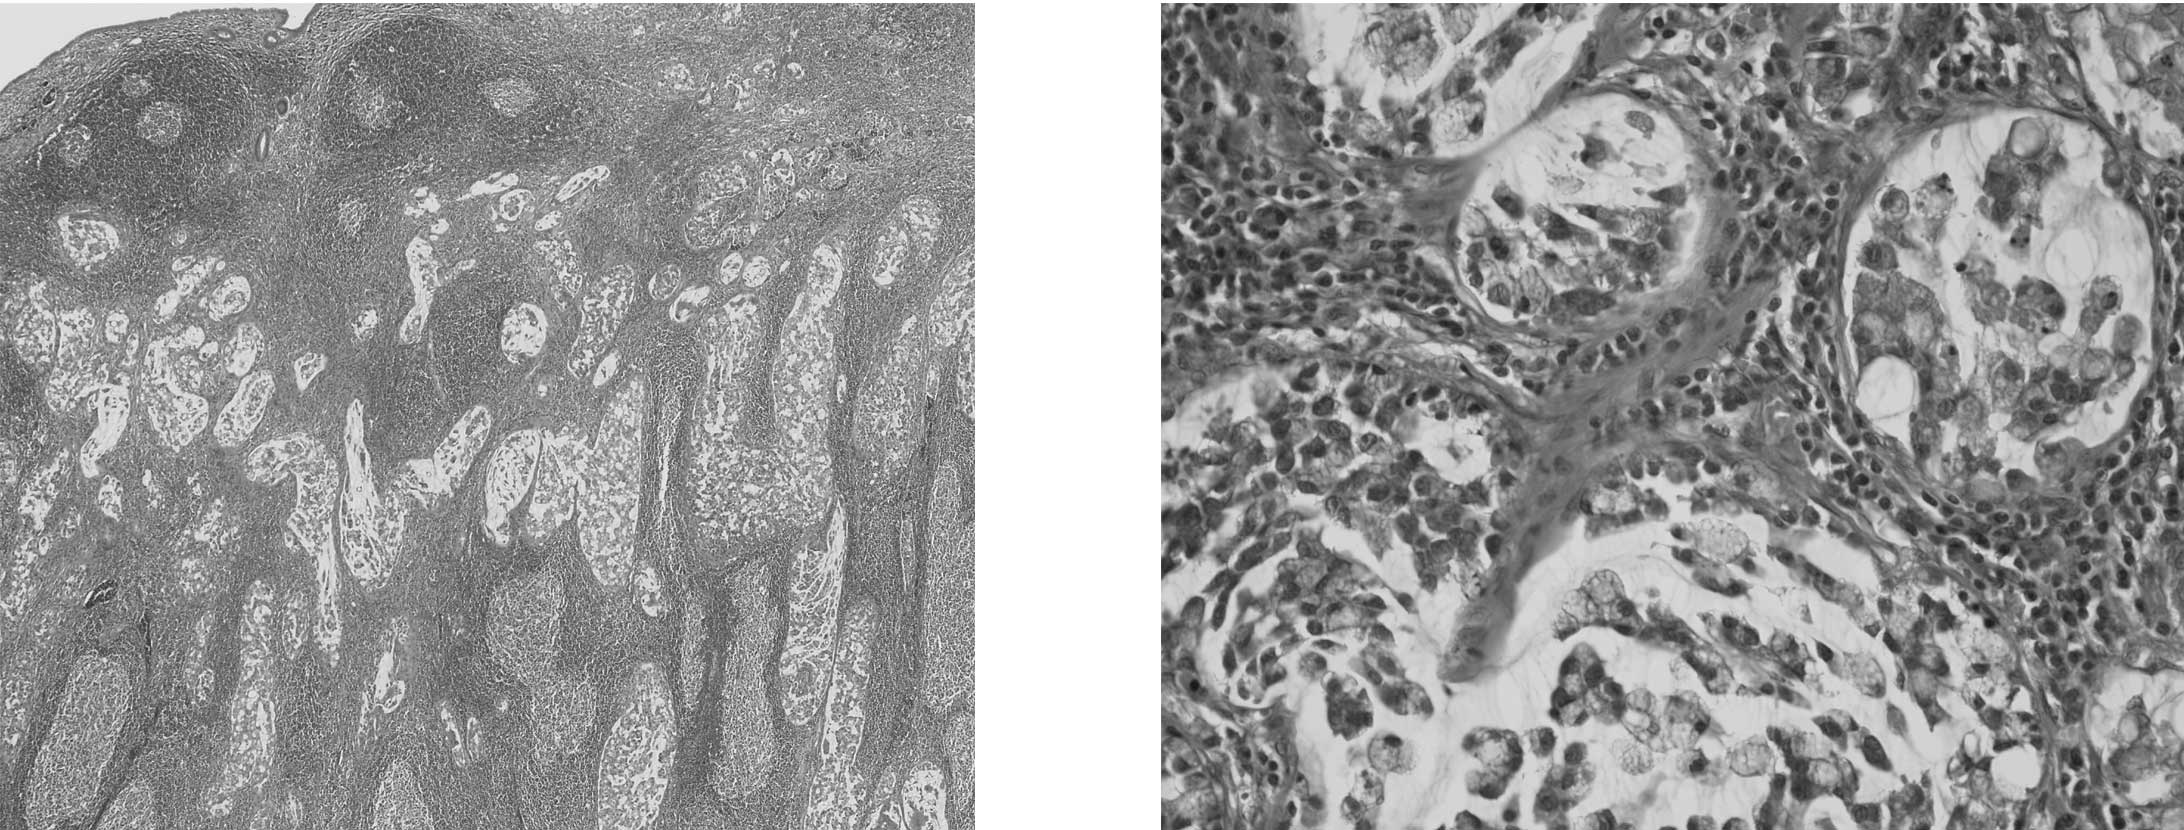

Histopathological study of colo-ileal carcinoma

Cases of colo-ileal carcinoma (CIC), defined as intestinal carcinoma involving the right-sided colon and the ileum, are rarely encountered. The aim of this study was to elucidate the clinicopathological characteristics, which have been poorly understood, in such cases. A total of 16 CICs were examined histologically and immunohistochemically. Microsatellite instability-related histology was also evaluated according to previously published models, such as MsPath and PREDICT. CICs included 14 adenocarcinomas and 2 mucinous adenocarcinomas. The CICs showed focal or diffuse cytokeratin 20 expression and 7 CICs showed focal cytokeratin 7 co-expression. MsPath and PREDICT scores ranged from 1.6 to 6.6 (mean, 3.14) and from 1.6 to 7.8 (mean, 3.86), respectively. Three CICs showed loss of MLH1 immuno­reactivity. Prominent neutrophilia and cancerous lymphangiosis in Peyer's patches (CLPP) were found in 8 cases (50%) and in 3 cases (18.8%), respectively. Neither variable was associated with parameters such as gender, tumor size or poor prognosis. However, the PREDICT score in prominently neutrophilic CICs was significantly higher than that in CICs with non-prominent neutrophilia (P=0.004). Patients with CLPP-positive CICs were significantly younger than those with CLPP-negative CICs (P=0.031). This study showed that almost all CICs originate from the right-sided colon with possible high levels of microsatellite instability. Prominent neutrophilia may be an additional histological indicator for microsatellite instability. Prognosis-independent CLPP occasionally occurs in younger patients with CICs.

Figure 1

Figure 2